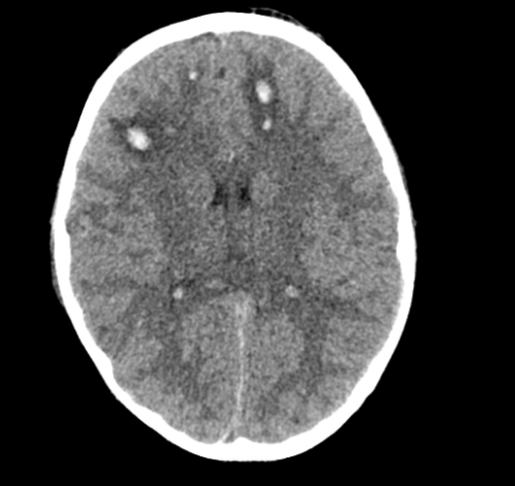

腦挫傷 - DAI

腦挫傷 - Hypoxic Encephalopathy

• 瀰漫性軸索損傷 (Diffuse axonal injury, DAI)

• 突然的加速、減速或旋轉力量導致腦組織剪切傷

• 造成許多小血管微出血

• 進一步導致腦皮質實質組織瘀傷